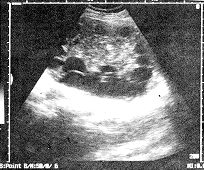

患者女性,40岁,因左肾包块5年伴左上腹胀痛一年来诊。无畏寒、发热,无肉眼血尿症状。查体:左上腹部隆起,扪及约10 cm×8 cm大小包块,质稍硬,境界不清,随呼吸活动。患者曾在农村生活多年,有牛羊犬接触史。化验检查:肝、肾功正常,尿红细胞25/ul。超声检查:左肾中上部探及11 cm×8.5 cm厚壁囊性肿块,壁厚0.6 cm,肿块中央为较多的实性成分,呈中等偏强回,其内可见散在钙化灶。周边绕以呈车轮状排列的小囊肿,大者直径约3.0 cm。彩色多普勒血流显像肿块内未见血流信号。左肾下极残存少量肾组织,见附图。超声诊断:左肾囊性为主肿块,考

虑为包虫囊肿。术中所见:肾脏呈囊状,大小12 cm×8 cm,皮髓质结构无法分辨。肾内含有数以百计黄豆至鸽蛋大小子囊,直径0.4~4.0 cm不等,囊内充满清亮液及粉皮样物。病理诊断:左肾包虫(细粒棘球蚴)病,肾实质压迫性萎缩;子囊囊液内可见退变坏死的细粒棘球蚴头节。

附 图